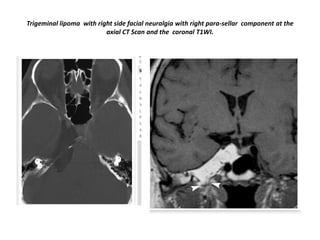

Trigeminal lipoma with right side facial neuralgia with right para-sellar component at the

axial CT Scan and the coronal T1WI.